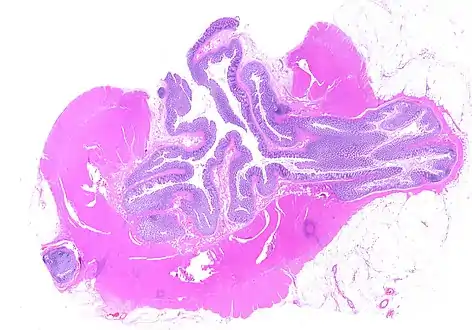

Whole slide of a transverse section of the left colon with diverticulosis

Diverticulosis is defined by the presence of multiple pouches (diverticula) in the colon.[22] In people without symptoms, these are usually found incidentally during other investigations.

While a good history is often sufficient to form a diagnosis of diverticulosis or diverticulitis, it is important to confirm the diagnosis and rule out other pathology (notably colorectal cancer) and complications.